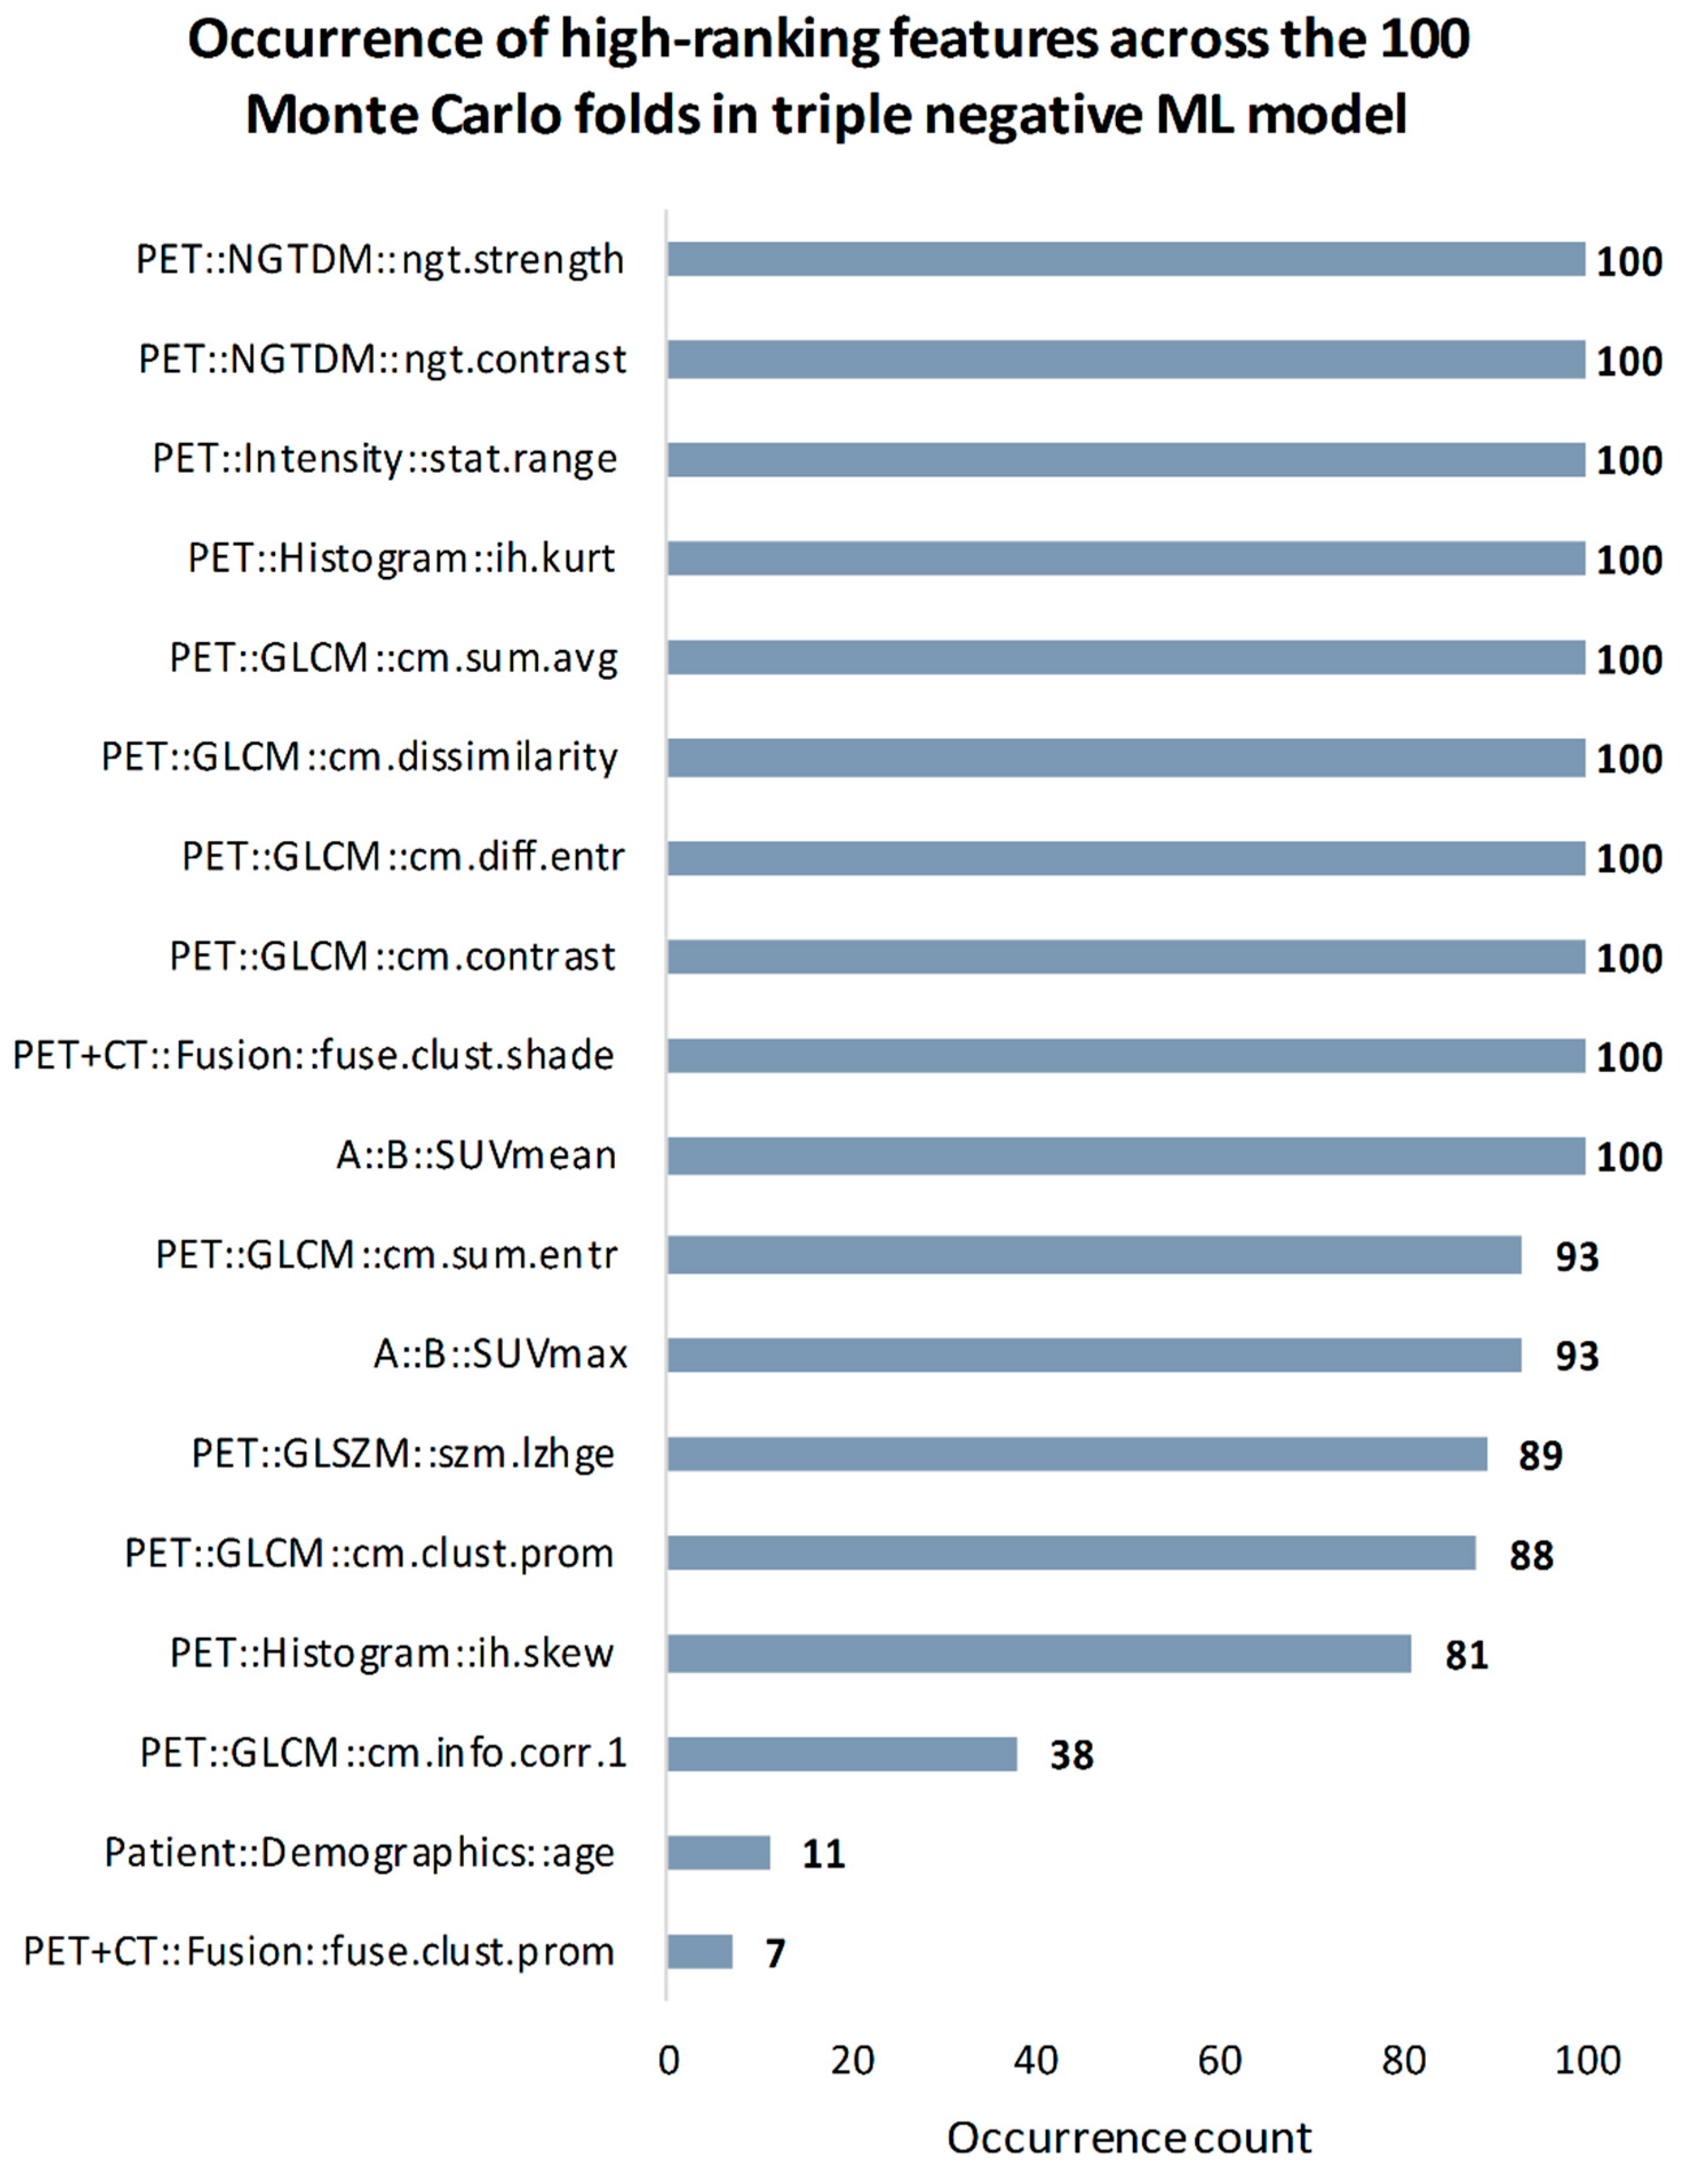

3.3.2. Breast Cancer Subtyping

3.3. Feature Importance Estimation